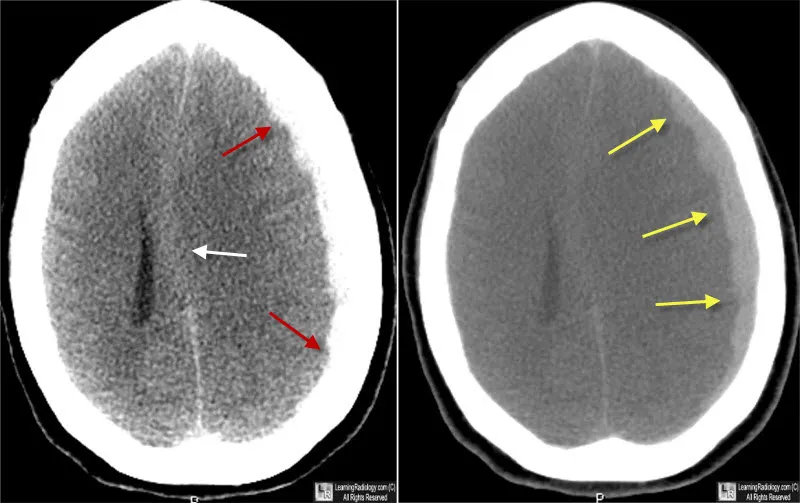

Intracranial Hemorrhages (ICH):

Feature Epidural Hematoma (EDH) Subdural Hematoma (SDH) Subarachnoid Hemorrhage (SAH) Intracerebral Hemorrhage (ICH) Vessel Middle meningeal a. (MMA) Bridging veins Arterial (e.g., aneurysm) Intraparenchymal vessels CT Biconvex (lens), no suture cross Crescent, crosses sutures Blood in sulci/cisterns Hyperdense in parenchyma Key Lucid interval Gradual onset, ↓LOC "Worst headache of life" Focal neurological deficits